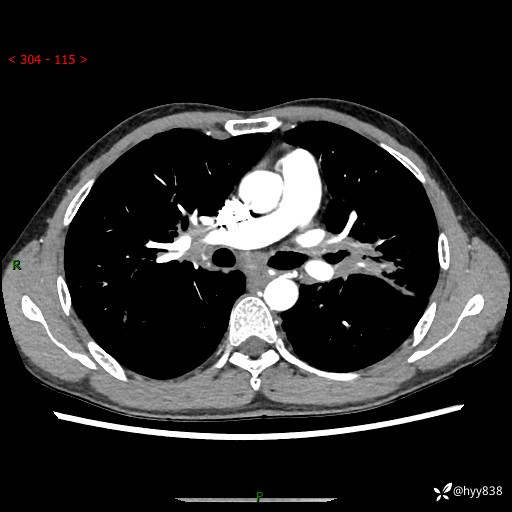

中年男性,咳嗽咳痰1月余。细看:肺、肺门、气管,貌似都有问题---(有结果)

现病史:患者于1个月前受凉后出现间断性咳嗽,伴白色泡沫样痰,无发热寒战、咯血、胸痛胸闷、恶心呕吐、呼吸困难等特殊不适,起初未予特殊处理,后患者就诊当地中医医院,查胸部CT提示支气管炎并双肺感染性病变,经抗感染(哌拉西林舒巴坦),止咳化痰(溴己新、三拗片)等治疗后,患者自诉咳嗽咳痰症状较前缓解,未诉发热等其他特殊不适,近期复查CT提示“肺部感染灶未见消退,双侧肺门增大,双肺散在小结节”,今为求进一步诊治,前来我院就诊,门诊以“肺部感染”收住入院。 患者自起病来精神、食欲、睡眠尚可,大小便正常,体力、体重无明显变化。

胸部CT平扫+增强(两期)